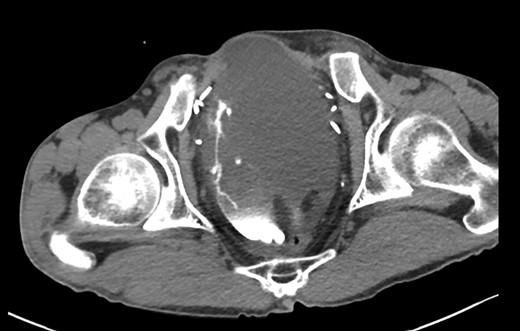

A 44-year-old male presented to Addenbrookes Hospital Accident & Emergency (A&E) Unit with two hours of abdominal pain, generalized distress, and peritoneal signs on physical exam. He has a history of extrophy-epispadias complex repaired as an infant. Due to persistent incontinence at the age of 36 years, he underwent cystectomy and formation of a cecal pouch with continent catheterizable appendiceal channel in the right lower quadrant. The patient reports catheterizing regularly with a 14Fr catheter, but was unable to catheterize the pouch for 8 hours prior to presentation. Notably, the abdominal pain became severe after a cough at home. In the A&E unit, the channel was catheterized with a 12Fr catheter with 150 mL of urine drainage. An initial non-contrasted CT of the abdomen and pelvis demonstrated a large amount of free fluid within the abdomen. The CT was repeated with contrast injected into the pouch via the 12Fr catheter, which demonstrated an intraperitoneal rupture (Figs 1 and 2). The patient was taken emergently to the operating theatre and a midline laparotomy was performed. The rupture in the cecal pouch was 1 cm in diameter, located on the anteromedial and inferior aspect of the pouch, and repaired with 2-0 polyglactin suture in two continuous layers (Fig. 3). The pouch was water-tight on leak test with 600 mL of normal saline. The pouch was kept to continuous drainage with a 14Fr Foley through the continent catheterizable channel. The Foley placement was confirmed intraoperatively by palpating the catheter in the pouch. A peritoneal drain was placed in the left lower quadrant. The midline fascia was closed with continuous 1-0 non-absorbable monofilament suture and the skin was closed with 3-0 polyglactin suture. The patient was taken to intensive care postoperatively and made an uneventful recovery.